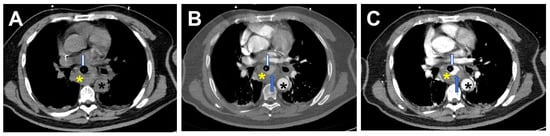

2. Case Report